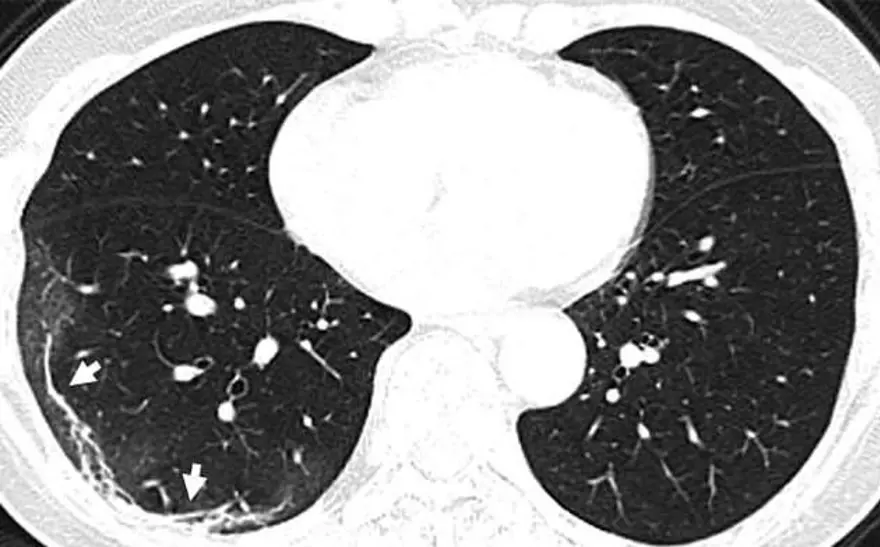

Wuhan'a seyahat ettikten sonra corona virüse yakalanan 54 yaşında bir kadının bilgisayarlı tomografi taramaları da akciğerlerinde hava boşluklarının kısmen dolduğunu gösteriyor.